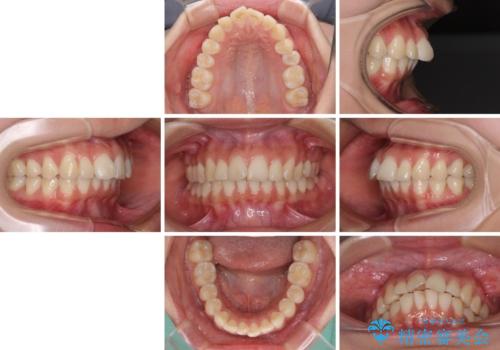

- 口を閉じたときに唇の間から飛び出してくる前歯を気にして来院された患者様です。

骨格的に上顎骨が前方位にあるため、左右の第一小臼歯を抜歯し、ワイヤー装置にて咬み合わせを整えていくこととしました。

前歯の突出感が改善されるだけでなく、奥歯の咬み合わせも改善され、食いしばりをしにくい状態に仕上げることができました。